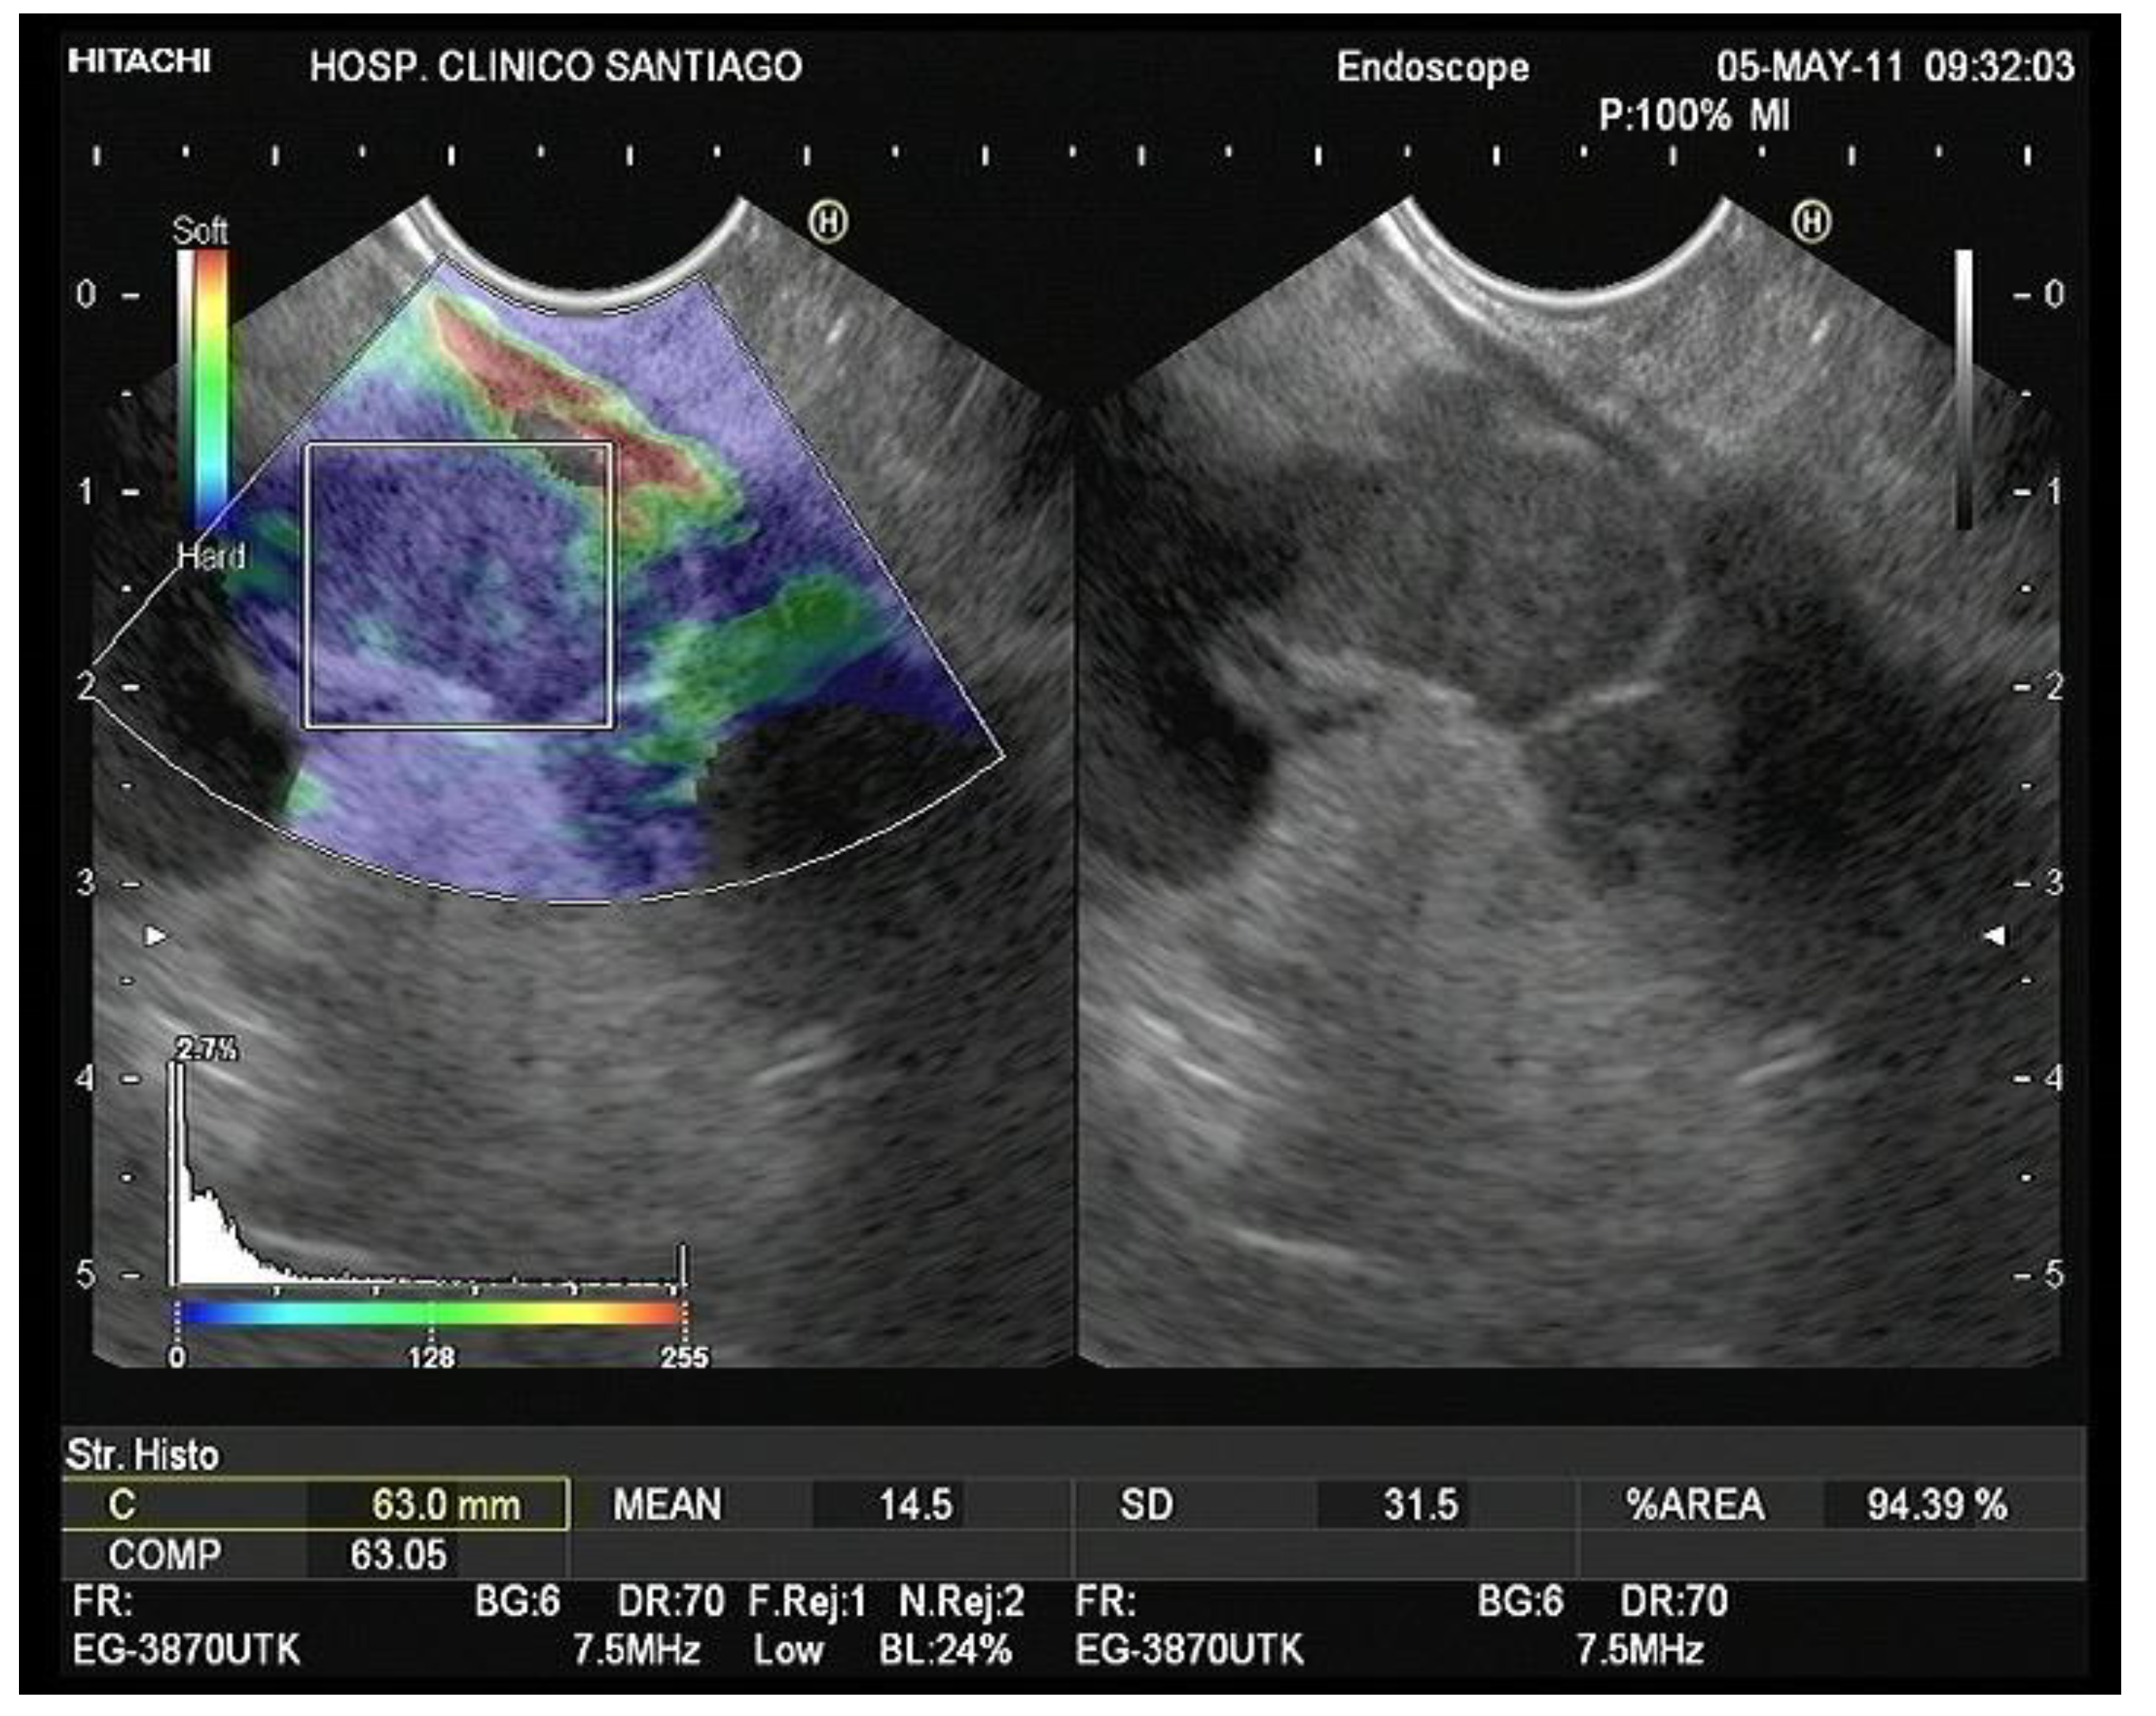

- Strain Histogram